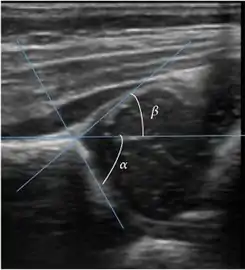

Ultrasound allows categorizing pediatric hips, according to Graf’s criteria, in four main types: normal, immature, and dysplastic (subluxed and dislocated). This classification is based on measurements of the acetabular inclination angle (alpha), cartilage roof angle (beta), and infant age. The femoral head coverage can also be determined by dividing the length of the femoral head covered by the acetabular fossa and the diameter of the femoral head. Its lower normal limits are 47% for boys and 44% for girls (Figure 11).[1]

Useful ultrasound measures in neonatal hip sonography, alpha and beta angles.[1]

Measurement of femoral head coverage.[1]